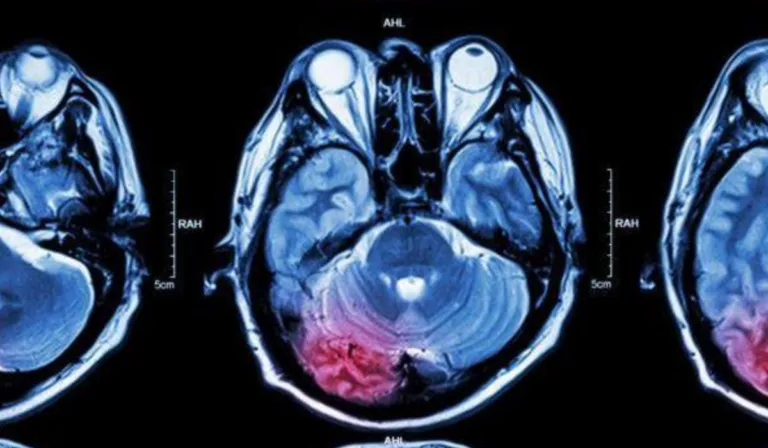

El implante, del tamaño de una moneda, se coloca en el cráneo y cuenta con ocho electrodos que se sitúan en la zona del cerebro encargada del movimiento. Cuando el usuario imagina mover la mano, el sistema envía señales a una computadora que las convierte en acciones reales.